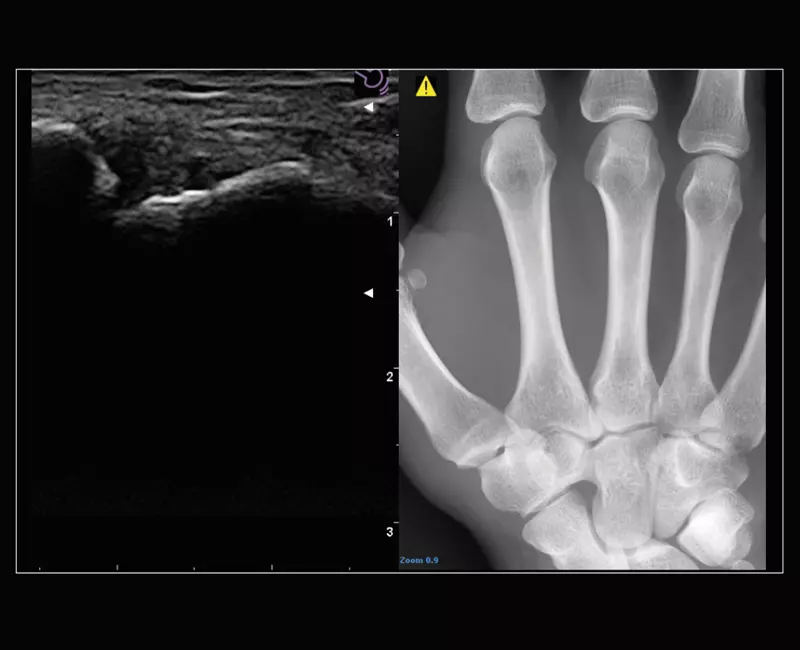

Wählen Sie aus einem großen Sondenangebot. Schallköpfe sind das Herzstück der Ultraschalltechnologie. Das Design, das Material und die Fertigungstechnologie von Schallköpfen bestimmen die Bildqualität eines Ultraschallsystems. Dank der Innovation von Goldstandard-Ultraschallköpfen bieten iQProbes eine Bildgebung nach dem letzten Stand der Technik.